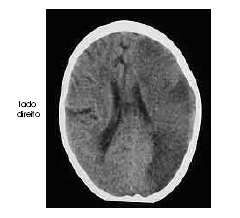

Um homem com 67 anos de idade, lavrador, deu entrada no pronto-socorro após ter sido encontrado, em sua casa, no chão e com dificuldade para falar e deambular. O paciente morava sozinho e os parentes não sabiam informar sobre uso de medicações ou patologias pregressas. Na avaliação, o neurologista identificou afasia mista, hemianopsia homônima direita e hemiparesia direita de predomínio braquifacial. Apesar de apresentar sonolência, o paciente ficava alerta ao chamado. A pressão arterial era de 180 mmHg × 90 mmHg. Foram solicitados exames complementares e de imagem, dos quais uma das imagens é reproduzida abaixo.

A partir da imagem retratada na figura acima, é correto inferir que se trata de acidente vascular cerebral com alteração de densidade à tomografia de extensa área de parênquima cerebral, razão por que deve ser contra-indicada a realização de trombolítico intra-venoso.

É possível relacionar o quadro clínico em questão a doença vascular em território da artéria cerebral média esquerda.